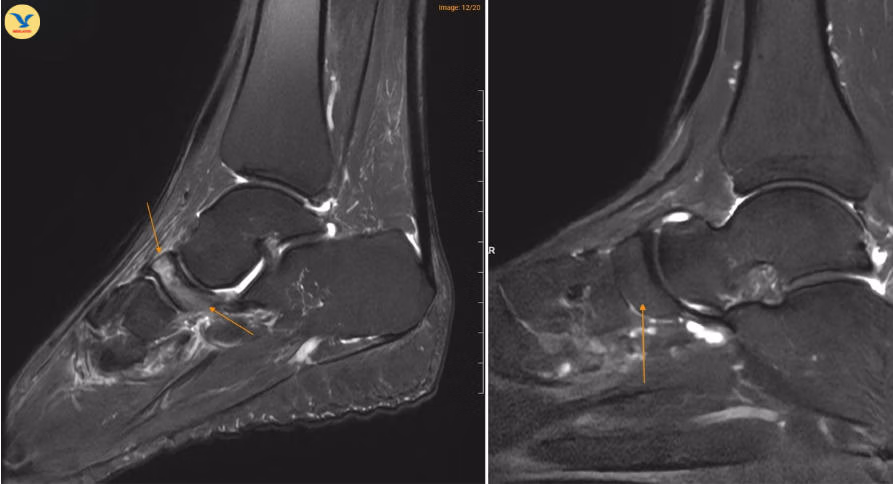

Tại MEDLATEC, bác sĩ đã chỉ định chụp Cộng hưởng từ (MRI) để tìm kiếm những tổn thương sâu trong cấu trúc xương. Trên lát cắt Sagittal T1W, hình ảnh cho thấy xương ghe bị xẹp và biến dạng điển hình hình dấu phẩy, kèm theo tình trạng đặc xương dưới sụn. Trên chuỗi xung T2W FS, ghi nhận tình trạng phù tủy xương ghe rõ rệt.

Đồng thời ghi nhận hình ảnh tổn thương gai xương thoái hóa khớp cổ chân trái, ổ phù tủy xương vị trí xương sên, phù nề dây chằng chày mác sau, dây chằng sên mác sau, dây chằng gót chày và dây chằng tam giác cổ chân, dịch khớp cổ chân, phù nề phần mềm quanh khớp cổ chân.

MRI: Đây là phương pháp nhạy nhất để phát hiện bệnh ở giai đoạn sớm thông qua tín hiệu phù tủy xương (tăng tín hiệu trên STIR/PDFS) trước khi có biến đổi về hình thái xương, đồng thời hỗ trợ đánh giá mức độ hoại tử xương.